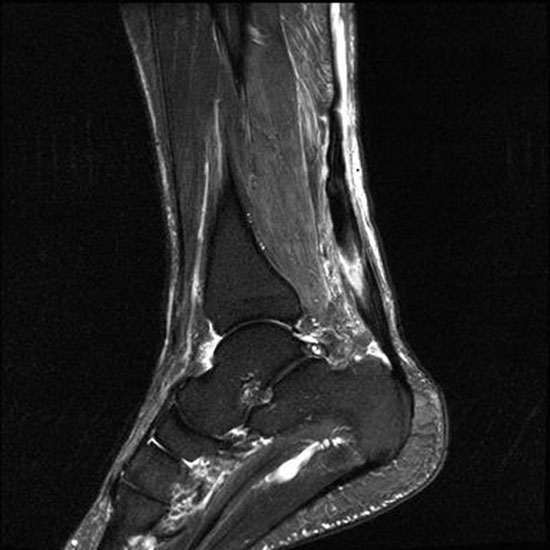

Hier befindet sich ca. 3-5 cm proximal des Tuber calcanei ein als „kritische Zone“ benannter Bezirk, der durch eine ungünstige arterielle Blutzufuhr gekennzeichnet ist (letzte Wiese). Hier finden sich häufig spindelförmige Schwellungen, die bei MRT-Diagnostik nicht selten partielle Nekrosen und Partialrupturen der Achillessehne aufweisen (Abb. 14).

Unabhängig davon können insbesondere chronische Insertionstendinosen der Achillessehne von Partialrupturen (Abb. 15) und erosiven Läsionen des dorsalen Fersenbeines begleitet sein.

Die sonographische Diagnostik eignet sich primär zur Erkennung schmerzhafter Prozesse im Verlauf der Achillessehne und kann bei Bedarf durch Röntgen bzw. MRT ergänzt werden. Besonders bei längeren Verläufen und kräftigen spindelförmigen Schwellungen (>9mm, Normwert <5mm) im Bereich der kritischen Zone sollte ein MRT zum Ausschluss von Nekrosezonen und Partialrupturen vor Therapiebeginn veranlasst werden. Die sonographisch leicht zu erfassende Veränderung der Sehnendicke im mittleren Sehnenanteil ist ein guter Indikator für die Schwere der Erkrankung und die Beurteilung des Behandlungsverlaufes. Die sichtbaren Veränderungen am distalen knöchernen Ansatz der Sehne sind diskreter.

Insbesondere bei größeren Partialrupturen (Abb. 14) sollten operative Verfahren erörtert werden. Kleinere Partialrupturen sind der ESWT gut zugänglich, wie die beiden nachfolgenden Beispiele zeigen: